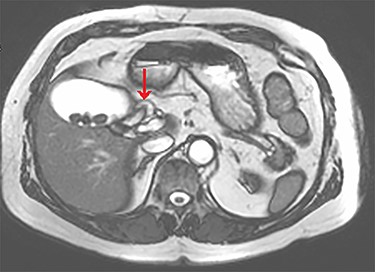

Axial view of the liver and gallbladder from a cardiac MRI showing the normal location of the cystic duct entering Hartmann’s pouch (highlighted by the arrow), which is separate and distinct from the structure shown in figure 1.

The tubular structure was remote from the porta hepatis with one lumen. It was located within the distal gallbladder fossa. Inspection of the gallbladder demonstrated an opening at the same orientation and of the same calibre as this tubular structure, raising suspicion for a duplicated cystic duct. Probing the source of the bile leak confirmed a single lumen. The capacity to perform IOC was not available at the time of the operation. A review of the patient’s prior imaging was performed. Recent cardiac magnetic resonance imaging (MRI), while not dedicated magnetic resonance cholangiopancreatography (MRCP), provided adequate views of the liver, gallbladder and biliary tree to demonstrate the suspected anomaly. On these images, two structures were seen to be connecting the gallbladder to the biliary tree. One duct was observed at Hartmann’s pouch, while a second connected to the gallbladder body (Fig. 1, Fig. 2). The images confirmed suspicion of a duplicated cystic duct and the decision was made to clip the lumen. The cholecystectomy was completed and a drain placed in the gallbladder fossa.